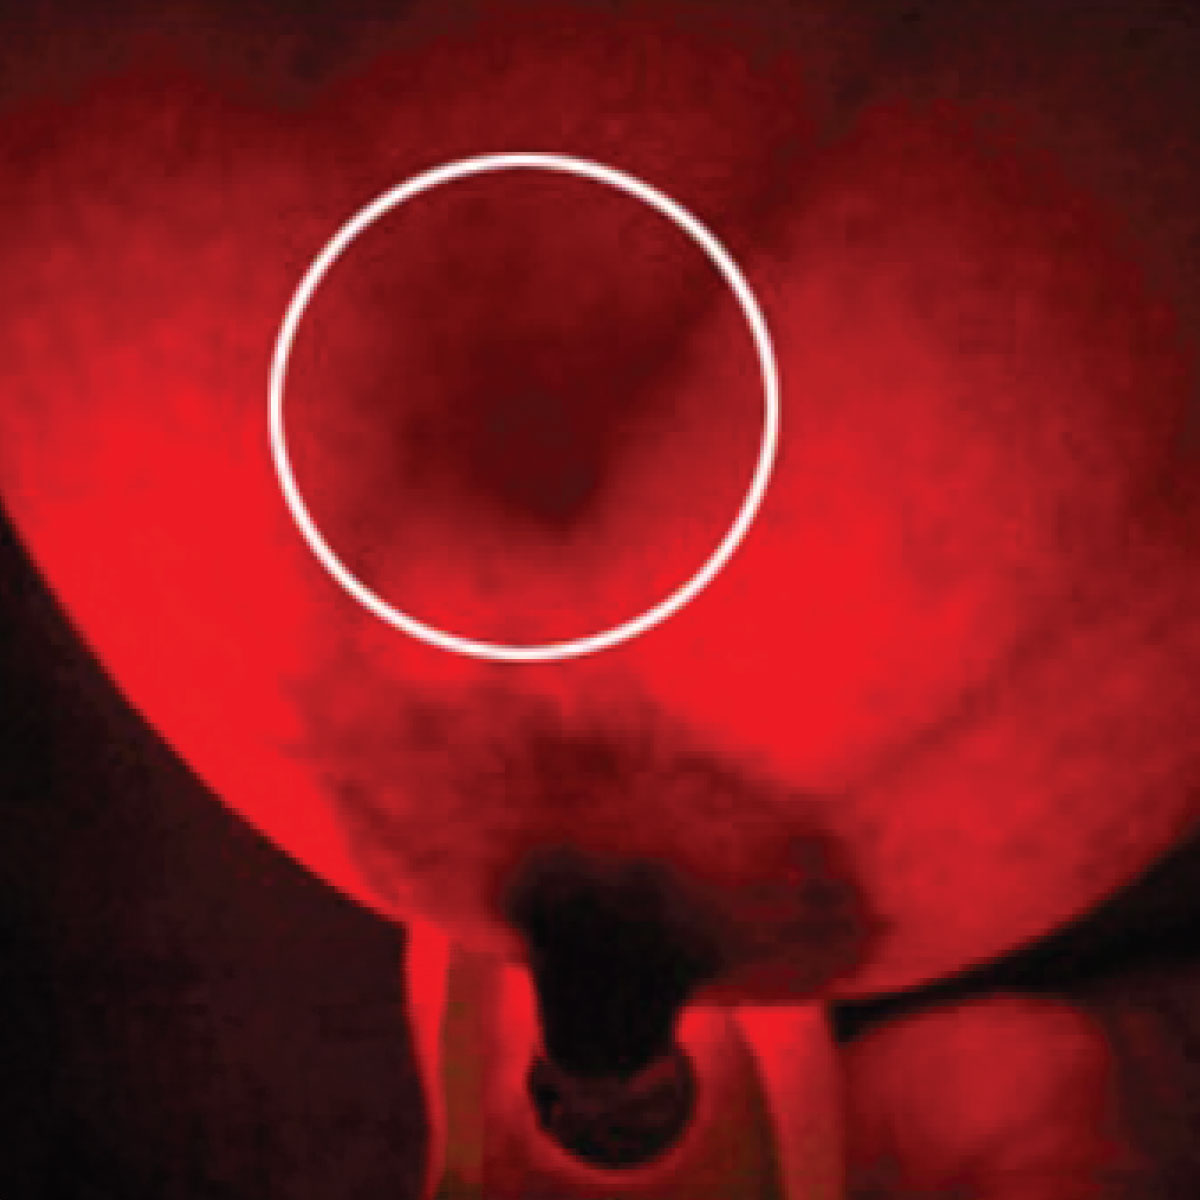

When using iSCANBREAST to scan your breasts, here's what to look for:

Healthy Breasts

Abnormal Breasts

The technology behind iSCANBREAST utilizes patented Red LED Technology, which emits a gentle yet penetrating light that allows users to visualize the internal structure of their breasts.

iSCANBREAST works by utilizing advanced LED light technology to provide a clear view of the internal structure of the breasts.

The device emits a gentle yet penetrating light that allows users to visualize breast tissue, facilitating early detection of potential abnormalities.